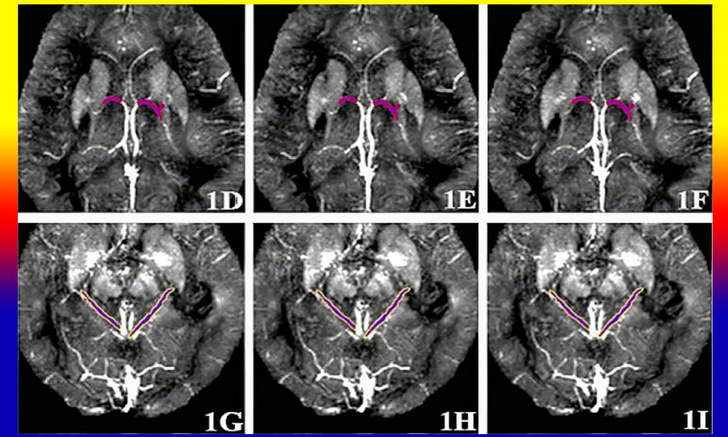

В основе методики — данные магнитной восприимчивости (МВ) вен головного мозга. Эта величина свидетельствует о толщине стенок сосудов и отслеживается по гемоглобину, сам он обладает низкой МВ. Соответственно, если толщина стенок вен нормальная, кровь по ним свободно циркулирует, гемоглобина достаточно, и МВ будет низкой. Если стенки утолщены, и просвет сосудов настолько узкий, что белка по ней проходит мало — МВ будет выше. Чтобы определить МВ, пациенту проводят МРТ с контрастным веществом, для этого исследователи подобрали специальный режим и мощность аппаратуры.

И одно из самых важных в разработке открытий — российские специалисты проанализировали данные 81 пациента с их согласия и определили, что базальные вены и вены таламуса в левом и правом полушарии головного мозга являются наиболее информативными для диагностики. До сих пор это было неизвестно. Высокое значение МВ в одной вене еще не означает наличия болезни, необходимо смотреть на все сосуды в обоих полушариях.